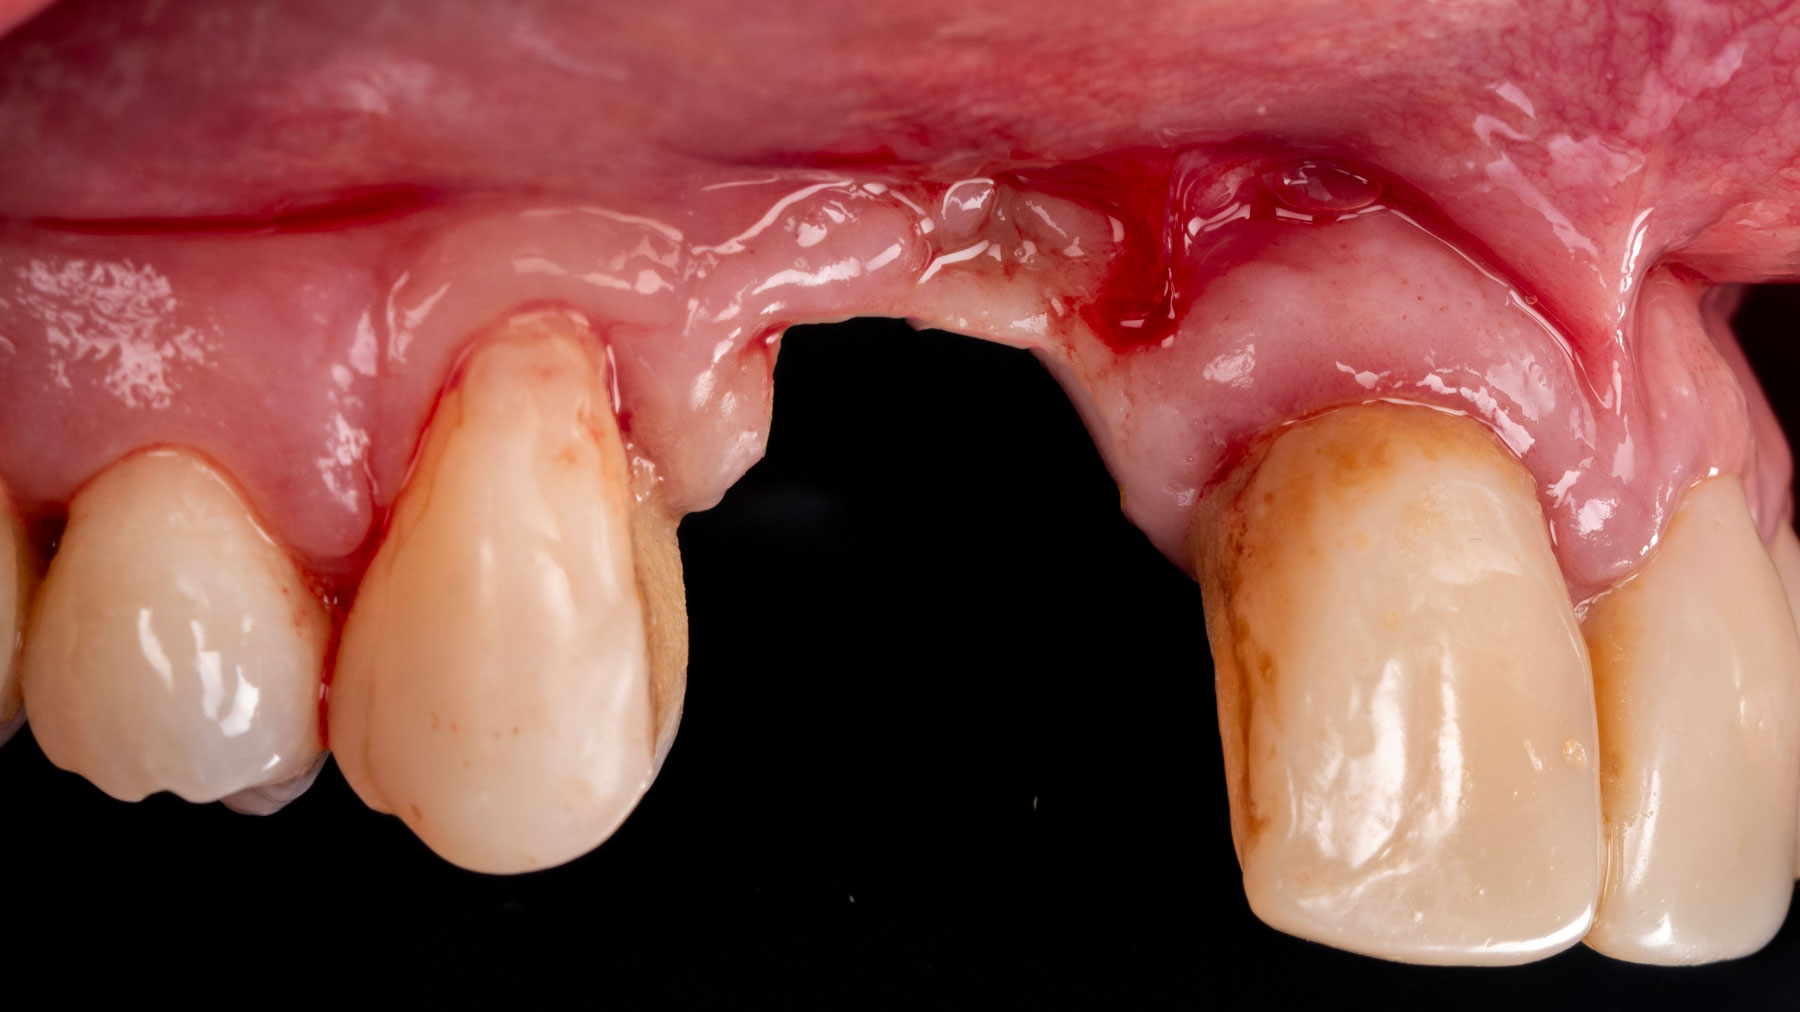

A patient presented with a vertical bone defect in the maxillary anterior region and expressed high esthetic demands while explicitly wishing to avoid autogenous grafting. This required a regenerative strategy that could reliably achieve vertical augmentation, maintain space, and deliver a stable peri-implant soft tissue phenotype—all without harvesting autogenous blocks or connective tissue.

Vertical ridge augmentation was performed using allogenic cortical plates fixed with microscrews to create a stable, space-maintaining box, which was densely packed with vallos® mineralized cortico-cancellous granules hydrated with the rhPDGF-BB component of GEM 21S®. Five months later, the implants were placed, and the peri-implant soft tissue phenotype was enhanced using Geistlich Mucograft® and Geistlich Fibro-Gide® to improve soft-tissue height and thickness.

Vertical ridge augmentation of the maxillary anterior was achieved using allogenic cortical bone plates fixed with microscrews to create a box configuration, filled with vallos® mineralized cortico-cancellous granules mixed with rhPDGF-BB component of GEM21S®. At implant placement, soft tissue phenotype was enhanced using Geistlich Mucograft® and Geistlich Fibro-Gide®.